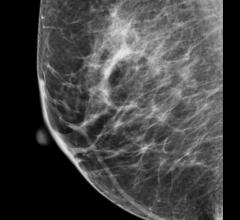

Mammography is a breast imaging technique that uses X-rays to diagnose and locate tumors of the breasts.

Despite decades of progress in breast imaging, one challenge continues to test even the most skilled radiologists ...